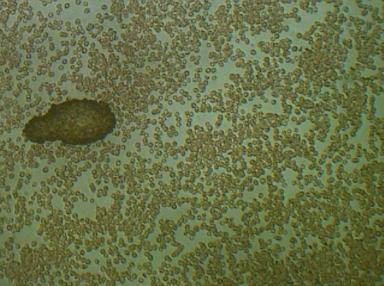

2.PASOŻYTY I GRZYBY

w zakwaszonym środowisku rozwijają się różnego rodzaju organizmy pasożytujące : robaki, grzyby, bakterie, wirusy i inne. Walka z nimi jest możliwa tylko przez zmianę środowiska z kwaśnego na zasadowe, w tym środowisku nie mogą się one rozmnażać i żyć.

We krwi widoczne są larwy i jaja pasożytów.

Komórki grzybów. W zależności od tego w jakim stopniu organizm zaatakowany jest przez grzyba widoczny jest obraz pojedynczych komórek lub całych kolonii i wtedy możemy mówić o bardzo niebezpiecznej dla organizmu grzybicy.